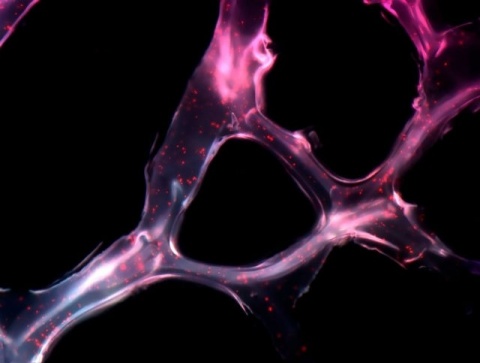

Pero el estudio también trajo un resultado alentador inesperado: los científicos constataron en el laboratorio que el extracto de palán-palán y moléculas purificadas (ácido palmítico y escopoletina) inducía la expresión de genes que disparan el suicidio programado o “apoptosis” de ciertas células tumorales humanas, mientras que reducían la actividad de genes que prevenían esa autodestrucción.

“Al final, todas las células presentes en el cultivo morían”, resumió Milanesi.